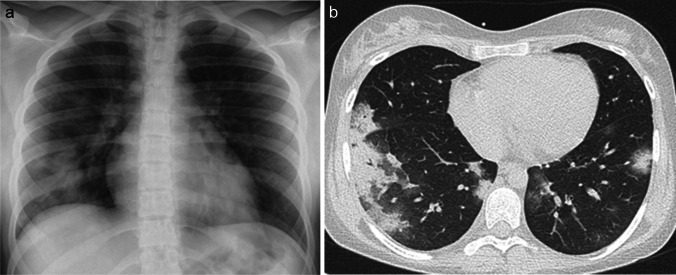

The clinical presentation and blood laboratory analysis of COVID-19 pneumonia is relatively nonspecific. Cough, fever, myalgia, and fatigue are the most common presenting clinical features. On imaging (Figs. 1 and 2), COVID-19 pneumonia in pediatric patients appears as unilateral or bilateral peripheral (subpleural) and/or posterior, and lower lobe-predominant hazy opacities with or without consolidation [19–22]. These findings can be detected on chest radiography; however, chest CT is more sensitive for detection and localization of the imaging findings of COVID-19 pneumonia, especially subtle ground-glass opacities which can only be detected on CT [23–26]. In addition, the CT halo sign is also considered a typical finding of the early phase of pediatric COVID-19 pneumonia [20]. However, the additional CT findings do not affect management in patients with mild to moderate symptoms; therefore, CT is not indicated in these patients and is only typically utilized in patients with a severe COVID-19 pneumonia [25]. Atypical imaging findings, including centrilobular nodules (including tree-in-bud nodularity), cavitation, pleural effusion, and/or lymphadenopathy, are uncommon findings in pediatric COVID-19 pneumonia. Consequently, when present, these atypical imaging features should raise strong consideration for alternative diagnoses [20].

Fig. 1.

Images in a 17-year-old girl with coronavirus disease 2019 (COVID-19) who presented with fever, cough, and fatigue. a Anteroposterior supine chest radiograph shows bilateral peripheral opacities predominately in the basal segments of the lungs. b Axial non-contrast-enhanced lung window computed tomography image shows the typical signs of COVID-19 in children: subpleural and peripheral consolidations in basal and posterior lung segments surrounded by ground-glass opacities (the halo sign)

Fig. 2.

Coronal (a) and sagittal (b) contrast-enhanced lung window computed tomography images in a 7-year-old girl with coronavirus disease 2019 show small ground-glass opacities (arrows) in the basal and posterior lung segments – these findings were not visible on radiography